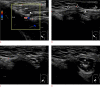

Inguinal hernia is the most prevalent type of abdominal wall hernia. Indirect inguinal hernia is twice as common as direct inguinal hernia. Computed tomography and magnetic resonance imaging can be used to evaluate inguinal hernia, but these modalities are greatly limited by their cost and availability. Ultrasonography has emerged as the most convenient imaging tool for diagnosing inguinal hernia due to its advantages, such as portability and absence of radiation. The present pictorial review presents an overview on the use of ultrasonography in the evaluation of inguinal hernia with a particular emphasis on the regional anatomy, relevant scanning tips, identification of subtypes, postoperative follow-up, and diagnosis of pathologies mimicking inguinal hernia.